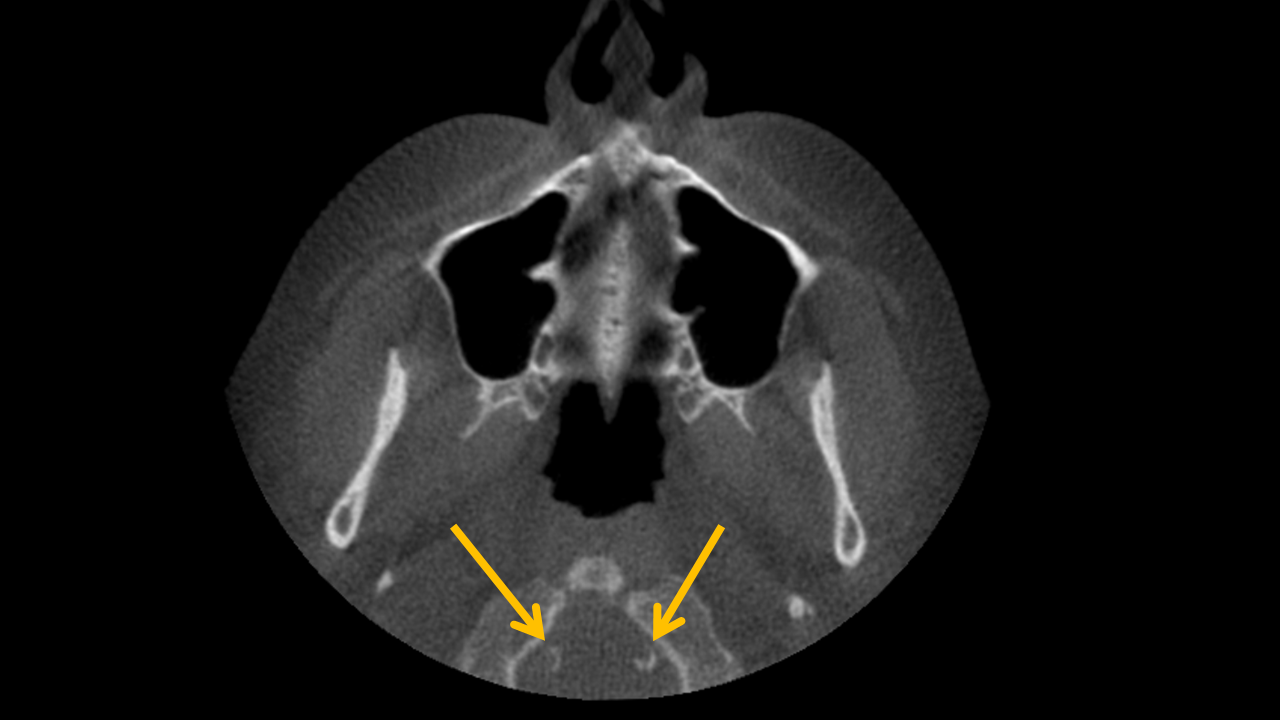

Axial CBCT scan showing vertebral artery region prior to identification of curvilinear radiodensities behind the anterior arch of the atlas Axial CBCT scan with highlighted curvilinear radiodensities posterior to the anterior arch of the atlas, indicating vertebral artery calcification

Study 1

Finding: Circumferential radiodensities within the soft tissues posterior to anterior arch of atlas representing vertebral artery calcification.